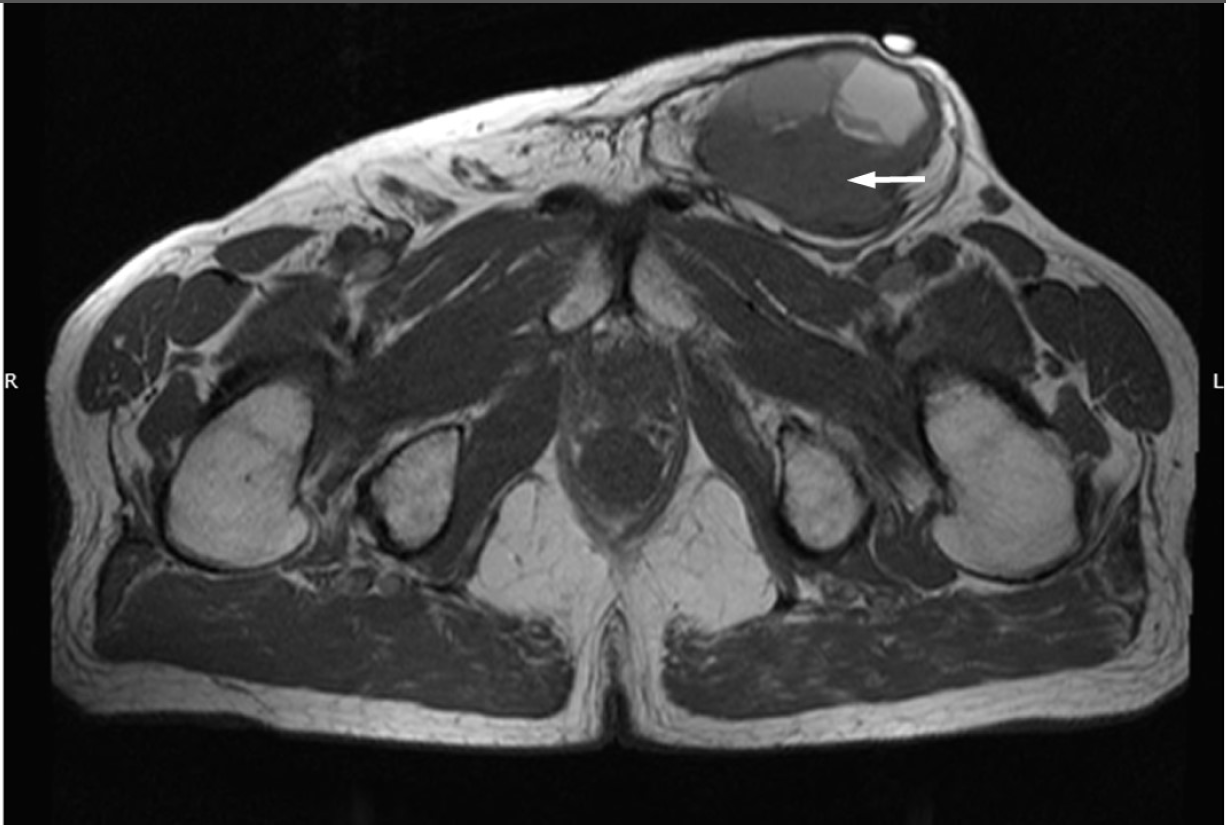

Evaluation of a Soft Tissue Mass in the Extremity or Trunk

- Multidisciplinary planning and use of core-needle biopsy for diagnosis of soft tissue sarcoma

- Impact of tumor grade and histologic subtype on outcomes for soft tissue sarcoma

- Development of molecular diagnostic testing for soft tissue sarcoma